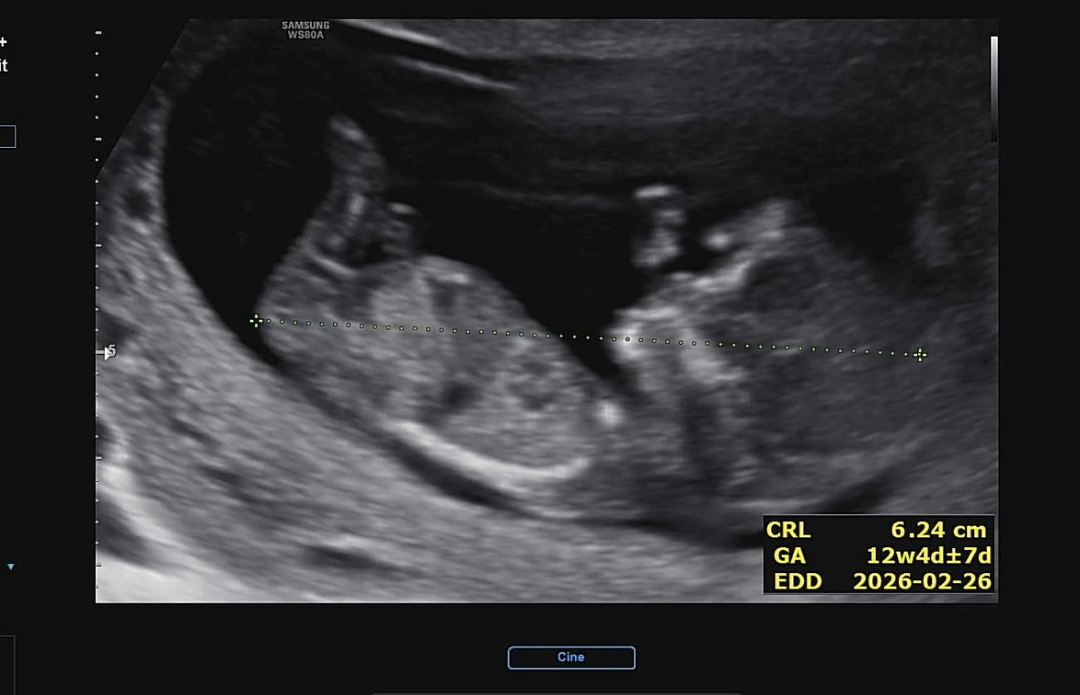

각도법 궁금해요!

각도법 궁금해요! 보이는 사진이려나요?